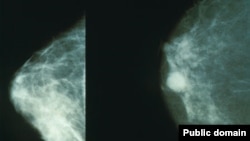

افغانستان کې د سینې سرطان د درملنې په هدف کمپاین پیل شو

د افغانستان د عامې روغتیا وزیر وايي، د روغتیا نړېوال سازمان د راپور په اساس افغانستان کې هرکال نېږدې ۲۰ زره کسان په سرطان اخته کېږي.

د عامې روغتیا وزیر فیرزوالدین فیروز د يکشنبې په ورځ په هېواد کې د سینې سرطان د تشخیص او درملنې په هدف د عامه پوهاوي د کمپاین د پيل پر مهال وویل چې په هېواد کې شاوخوا ۳۵۰۰ تنه د سینې په سرطان اخته دي چې ۱۷۰۰یې د مرګ له ګواښ سره مخ دي.

د افغانستان عامې روغتیا وزیر وویل،که د ثدیه يا سینې سرطان په وخت تشخیص او درملنه يې وشي د مرګ خطر کمولای شي.

په سینو او تخرګونو کې د غدو پيدا کېدل او د سینو د رنګ بدلون د سینې د سرطان عمده علایم دي چې ناروغ يې په لیدو باید ډاکټر ته مراجعه وکړي.